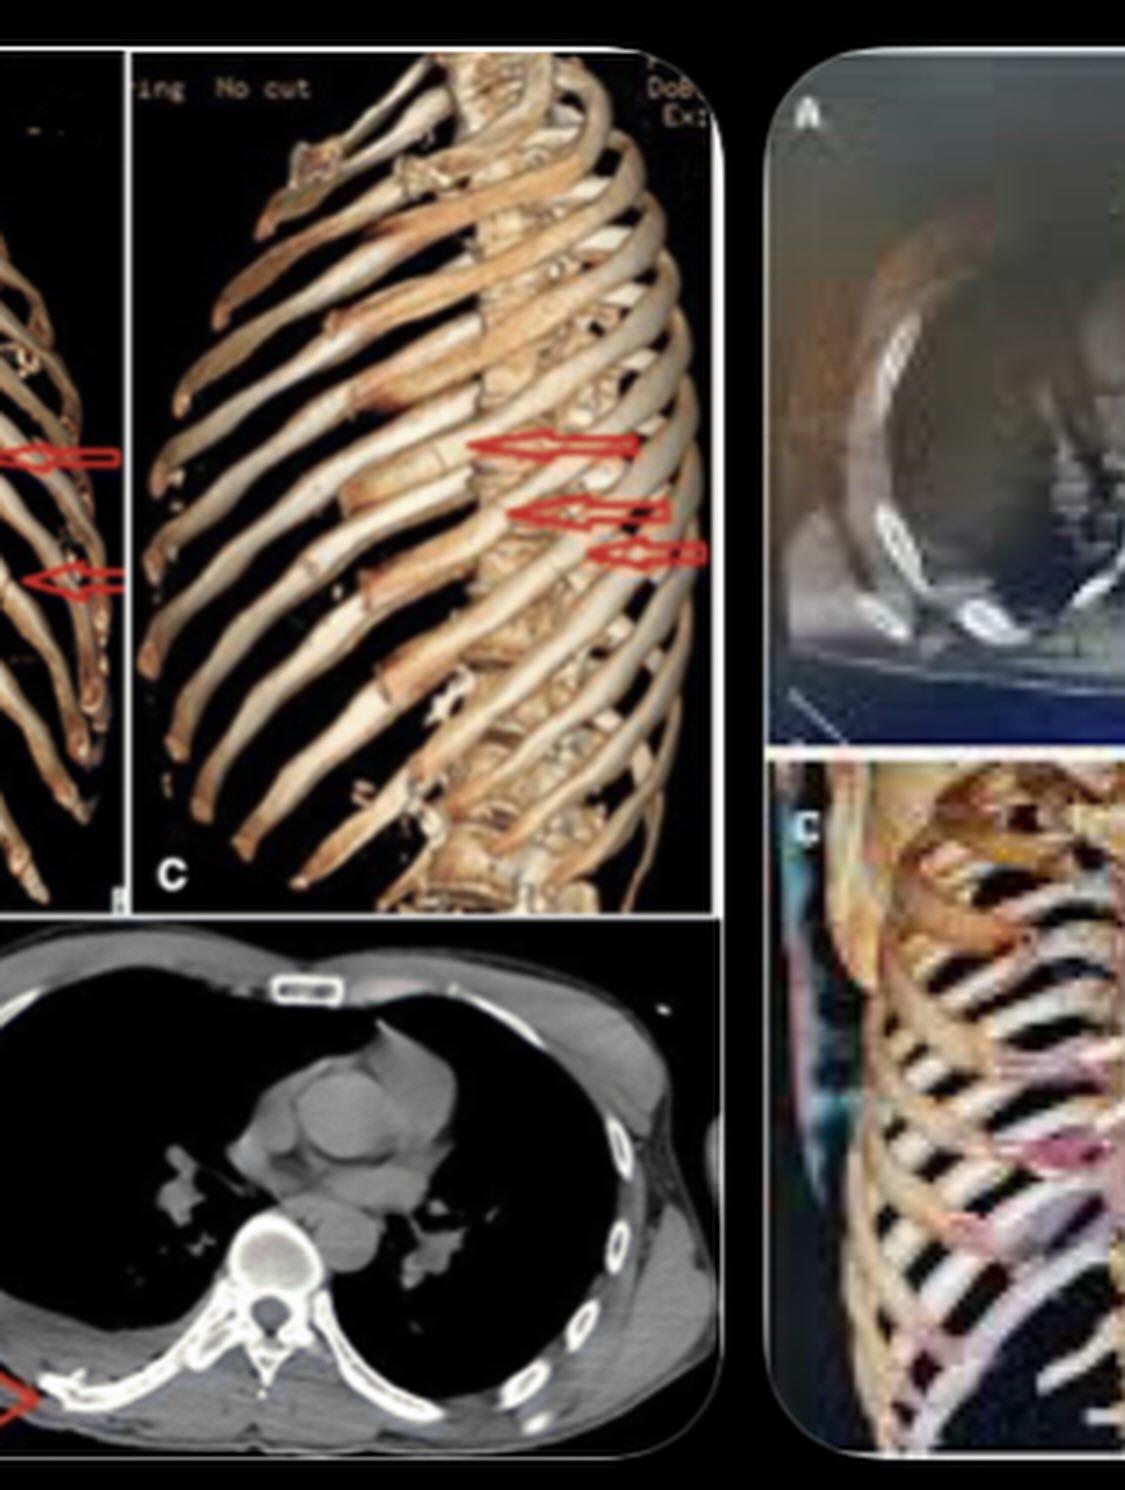

Entre las heridas reportadas se encuentran 11 costillas fracturadas, un pulmón perforado, conmoción cerebral y hemorragia interna, además de diversas lesiones en el rostro y otras partes del cuerpo.

En ese centro médico, los especialistas detectaron que una costilla desplazada estaba presionando uno de sus pulmones, por lo que fue sometido a tres cirugías adicionales y permaneció 18 días más hospitalizado.